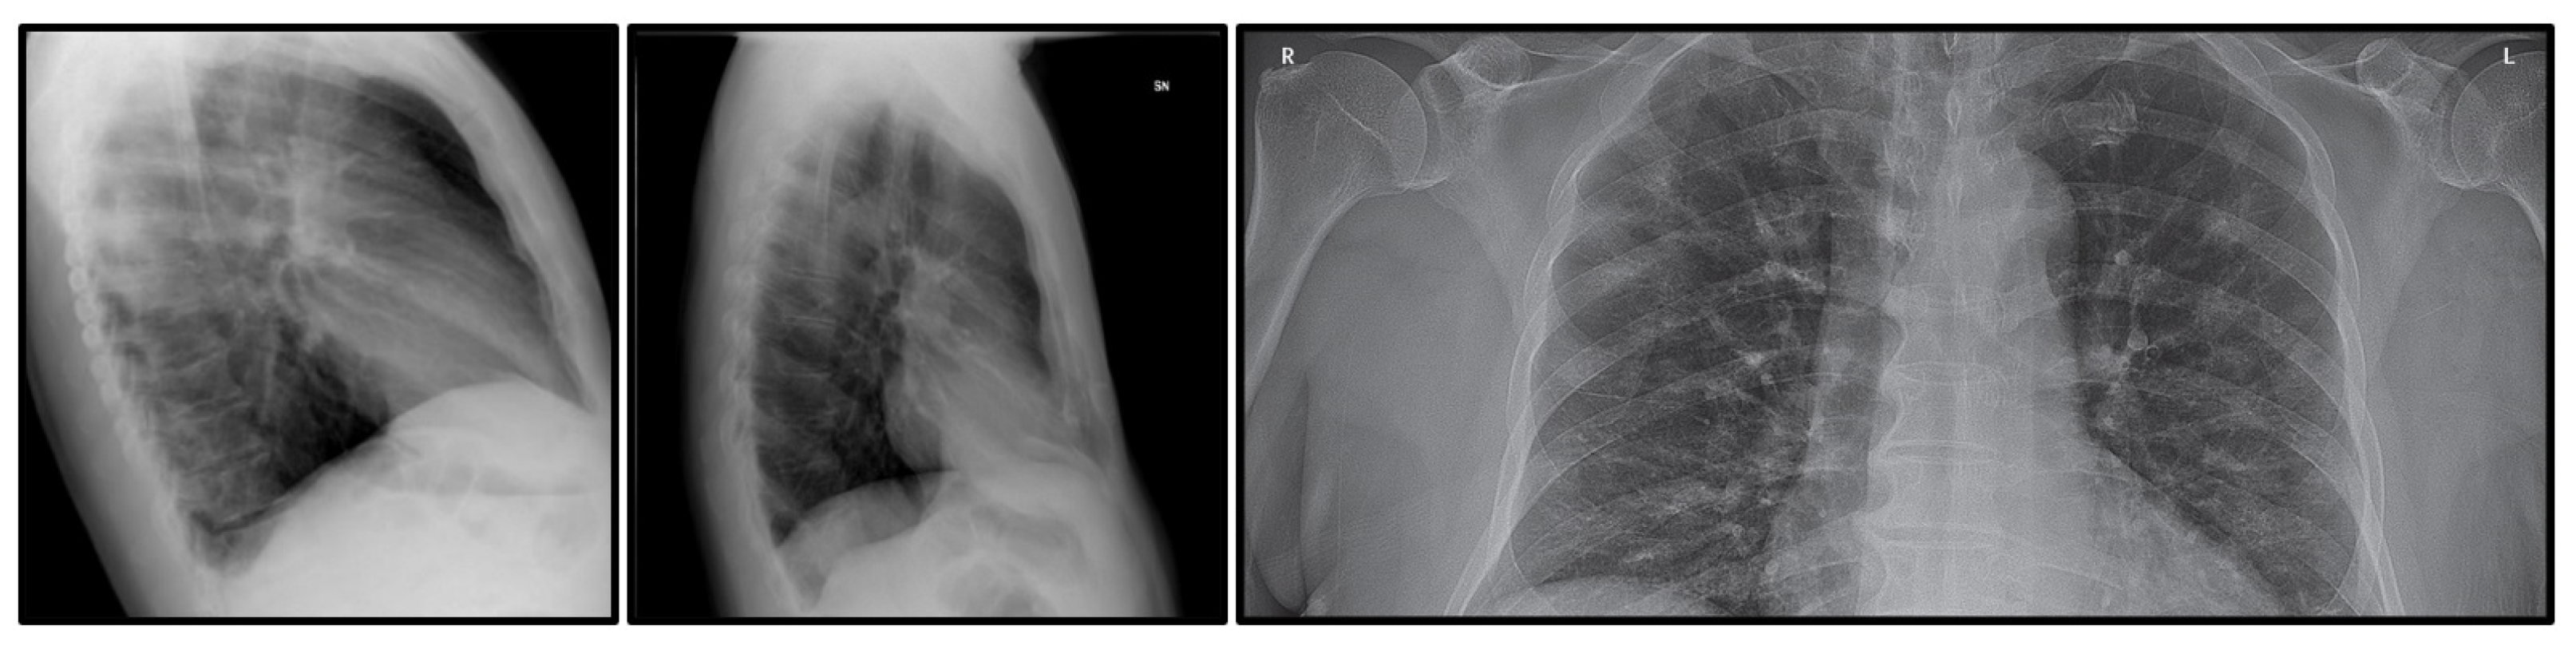

4.1. Dataset